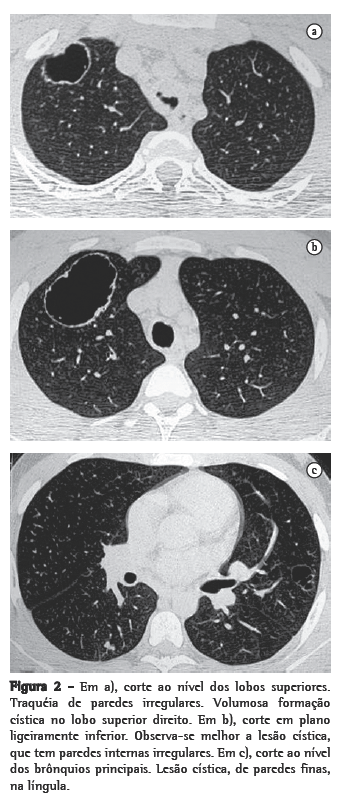

ResultadosNos 8 casos foram observadas na TC formações polipóides na traquéia. Em 1 deles, identificou-se também uma lesão em brônquio principal. Sete pacientes mostravam comprometimento do parênquima pulmonar. Em todos foram observadas lesões nodulares escavadas, com contornos internos irregulares, e paredes de espessuras variadas, com aspecto multilobulado em 6 casos, e com confluência das lesões em 5 deles (Figuras 1 a 5). Nódulos sólidos foram vistos em 6 pacientes, Em apenas 1 dos casos foram vistos níveis líquidos. As lesões predominaram nas bases em 3 pacientes, nos terços médios em 2, e em 2 não havia predomínio de distribuição. Em 1 dos pacientes, foi observada associação com massa, e em outro, com consolidação. Neste último paciente (Figura 5) foi constatada degeneração maligna em múltiplas lesões. Sinais de aprisionamento aéreo também foram observados em 1 caso. Em nenhum deles detectou-se linfonodomegalia ou derrame pleural.

A TC, particularmente com aquisição volumétrica (espiral), é superior às radiografias de tórax no reconhecimento de nódulos ainda pequenos, nas fases iniciais de disseminação pulmonar, por sua melhor caracterização e visualização de vegetações nodulares traqueobrônquicas. Os achados tomográficos incluem estreitamento nodular, focal ou difuso, da via aérea. Os nódulos crescem na superfície mucosa, e sua extensão intraluminar é melhor avaliada por TC.(3) São alterações facilmente correlacionadas à doença quando se dispõe da história clínica de papilomatose.(4) Outros achados relacionados à obstrução das vias aéreas e/ou infecções associadas são atelectasias, consolidações, aprisionamento aéreo e bronquiectasias.(2-4) Na nossa casuística, formações polipóides na traquéia foram observadas em todos os exames tomográficos. Sete pacientes mostravam comprometimento do parênquima pulmonar, caracterizado por lesões nodulares escavadas, com contornos internos irregulares, e paredes de espessuras variadas, com aspecto multilobulado e tendendo à confluência. Nódulos sólidos foram vistos em 6 pacientes. Em nenhum deles detectou-se linfonodomegalia ou derrame pleural.